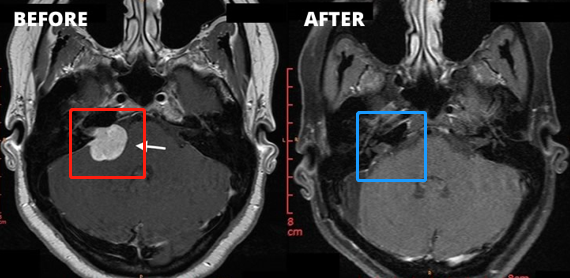

1、左侧图示(红色)患者术前核磁:右侧桥脑小脑角区见一类圆形占位性病变,边界清楚,T2WI高信号,其内信号欠均匀,增强扫描后病变呈明显强化,同侧桥脑小脑角池扩大,内听道扩大,四脑室轻微受压。

2、右侧图示(蓝色)患者术后核磁:术后肿瘤切除干净,做到了全切全切,核磁未见占位性病变。与术前对比明显可见肿瘤完整切除,较大限度减少复发可能。

3、患者术前情况:右耳耳鸣3个多月,听力下降,头昏头痛加重。面肌抽搐、舌头、牙龈和脸有麻木感觉,无法正常生活。

4、患者术后情况:术后1周出院,术后2周面神经功能House-Brackman分级1级。面神经保留,没有面瘫,听力保留。术后9个月随访,恢复很好,能够正常生活。

5、手术总结:听神经瘤切除手术规模较大的挑战是确定90%以上切除率的同时,既不损伤听神经、听力,也不损伤面神经,不会发生面瘫。以上肿瘤全切术由巴特朗菲教授操作,术后听力保留较好,且无面瘫。这样的手术效果堪称,这样的技术手法和水平即使是国际神经外科医院案例中也可以作为教科书级别的案例。